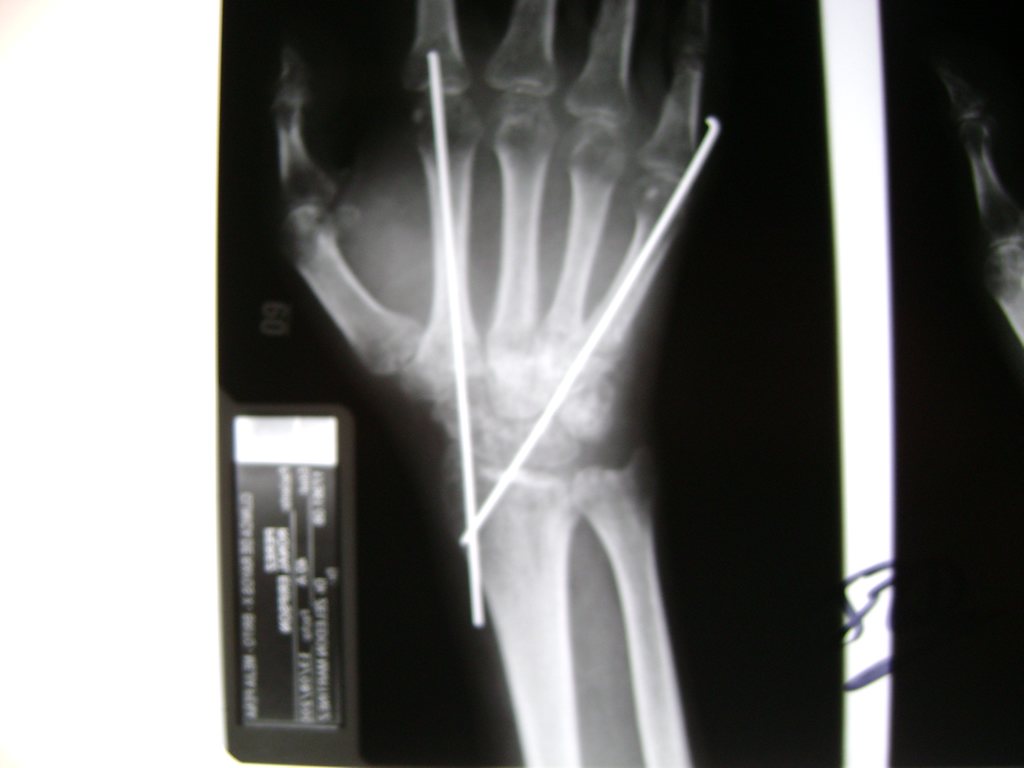

Cirugías de Codo - Cirugías de Muñecas y Manos

Los procedimientos más comunes en cirugía de la mano son aquellos destinados a reparar traumatismos, incluyendo lesiones de tendones, nervios, vasos sanguíneos, y articulaciones; huesos fracturados; y quemaduras, cortes, y otros daños de la piel.